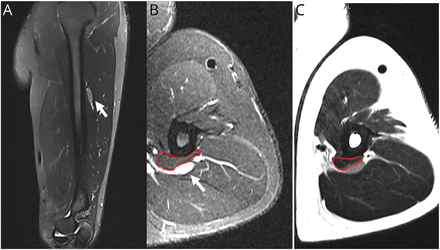

(一)矢状搅拌轴向搅拌(B)和(C)轴向T2图像。桡神经(白色箭头)局部增厚和增加信号的中间三分之一的肱骨。一个附属肱三头肌的肌腹(红线;B, C)是可视化压缩桡神经。搅拌=短τ反转恢复。